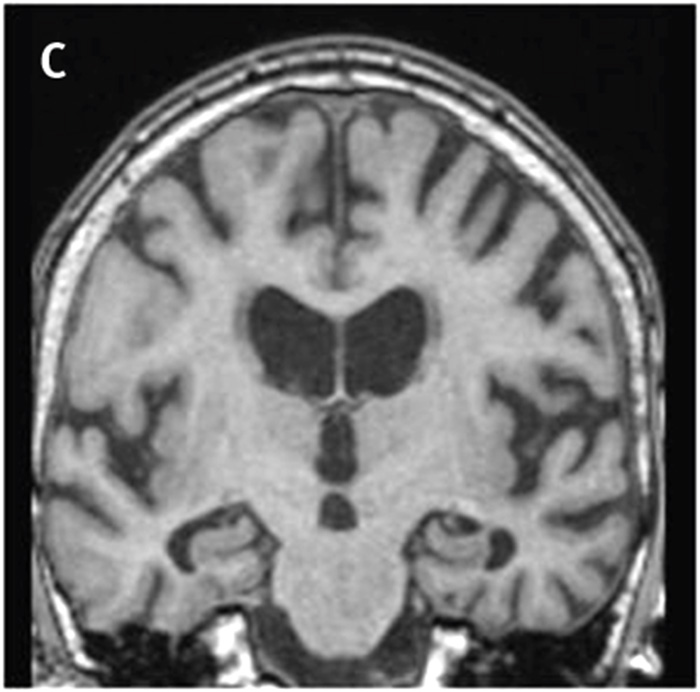

Global kortikal atrofi, GCA. Visuell bedömning av kortikal atrofi speglar inte bara den totala cerebrala atrofigraden utan även den lobära och den regionala atrofigraden. Vidgning av sulci på MR eller DT kan vara sekundär till atrofi av kortex och/eller vit substans, varför beteckningen kortikal atrofi egentligen endast bör användas när man mäter tjockleken på kortex. Vidgning av sulci och volymförlust av gyri bedöms enligt en 4-gradig skala, GCA 0–3 [19]. Normala förhållanden utan vidgning av sulci är GCA 0, lätt vidgning av sulci är GCA 1, volymförlust i gyri är GCA 2 och uttalad vidgning av sulci med uttalad volymförlust är GCA 3 (Figur 3).

Figur 3. Global kortikal atrofi: GCA 0 (A) , GCA 1 (B) , GCA 2 (C)  och GCA 3 (D),  endast bifrontalt.